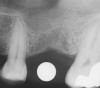

First, a periapical radiograph is taken to determine the amount of bone subantrally. It should be noted that a periapical film has an average error of 14%.23 Therefore, it is advantageous to take the radiograph in a manner that includes a marker (5-mm wide ball bearing) in order to be able to calculate the magnitude of radiographic error (Figure 1).

Figure 1  At tooth site No. 14, a periapical radiograph was taken with the long-cone paralleling technique. The radiographic ball marker measured 5.8 mm while its actual diameter is 5 mm. The enlargement is 0.8 mm, therefore the magnification error is 0.8/5 = 16%. By correcting for this error, a closer approximation of the amount of bone from the osseous crest to the sinus floor can be made.

Figure 1